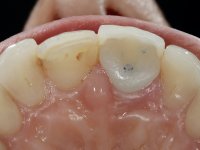

52-year-old female patient, non-smoker. He used an appointment with an implant already placed in the 1.1 site. It was provisionally rehabilitated with a composite resin crown adhered to the palatal surface of the adjacent teeth. This provisional had taken off several times in the last month, even in this first consultation it was taken off. We took advantage of this situation and verified that the “Tissue Level” implant had 2 to 3 mm of prosthetic space available. A deep bite and the inclination of the long axis of the implant posed a very difficult situation for the rehabilitator. If one chooses a abutment with a cemented crown, the height of the abutment would be minimal, with no retention or resistance. If a screwed solution is chosen, the screw access hole would emerge through the vestibular surface. It should be remembered that in 2006 the prosthetic solutions for this situation were limited to these options: 1- Screw-retained angled metal abutment for cemented crown 2 - Screw-retained angled metal abutment for transversally screw-retained crown 3 – Syn Octa metal abutment for screw-retained crown. A serious problem in this rehabilitation was guessed right from the start. The patient had a thick gingival phenotype and good oral hygiene.

After the impression of the implant using a double-mix technique with double viscosity and the collection of shape and color information by the ceramist, we proceed with the work. In the model, a syn octa was placed over the implant, and a screw was placed on it to assess its emergence in relation to the incisal edge. Then, an adequate emergence profile in the artificial gingiva was prepared. A abutment with characteristics suitable for overbite and simultaneously capable of receiving a veneer was waxed on top of this scenario. This waxing gave rise to the manual milling of a very personalized abutment. An infrastructure in Zr was also made for the veneer with a very great adaptation to the abutment. On this infrastructure ceramics were placed. Ceramic fluorescence sought to compensate for the lack of fluorescence that Zr had and obviously further customize the aesthetics. The adhesive bridge was removed and the definitive work was placed. The syn octa was initially tightened with 35 N to the implant and then the Zr abutment was tightened over the syn octa with 15 N. The access hole was plugged and then the veneer was cemented with resin-reinforced glass ionomer. After 15 years, the patient returned to the consultation with tooth mobility. Fortunately, nowadays we have the possibility of having dynamic tightening wrenches that allow tightening screws with greater inclinations. An access cavity was made without damaging the incisal edge of the veneer. Tightening was done with a dynamic wrench with 15 N torque. The hole was covered with Teflon and filled with composite resin. This solution allowed the problem to be solved in a simple and economical way.